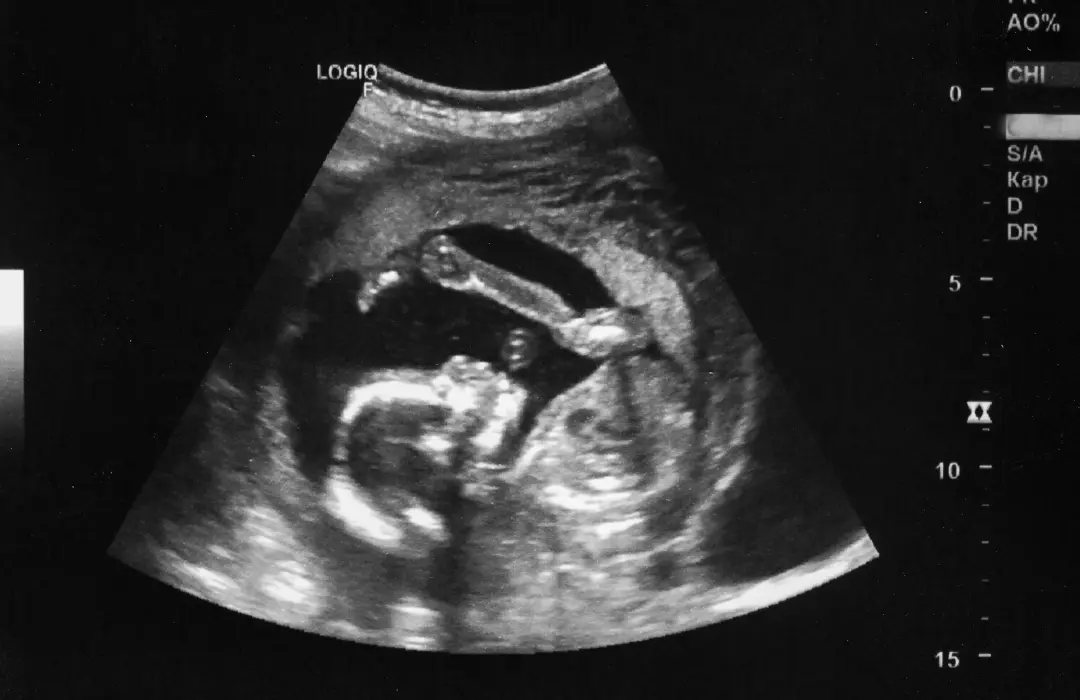

Semana 10 de Embarazo: El Cierre del Primer Trimestre y Pruebas Iniciales

En la semana 10, ya estás en la recta final del primer trimestre y tu bebé ha alcanzado un hito importante: deja de ser un embrión para convertirse oficialmente en un feto. Sus órganos vitales ya están formados y comienzan a madurar, su corazón late con fuerza y sus rasgos faciales son cada vez más definidos.

En esta semana, tu bebé deja de ser un embrión y se convierte en un feto, marcando un hito en su desarrollo. Su crecimiento es acelerado y sus órganos principales ya están formados, aunque seguirán madurando en las próximas semanas.

Aproximadamente el tamaño de una fresa (alrededor de 3-4 cm y 4-5 gramos).

Generalmente entre las semanas 11 y 14, para el ultrasonido de translucencia nucal.